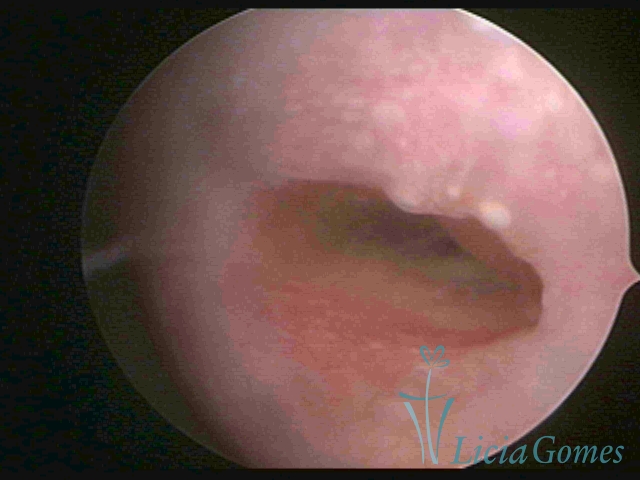

Second part or middle section

In the middle section of the cervical canal, the details of the buds are lost. It is possible to view creases and crypts. Longitudinal grooves are frequently observed. They are the most compact tissues presenting the most vascularized surface, whose vessels follow its passageway.